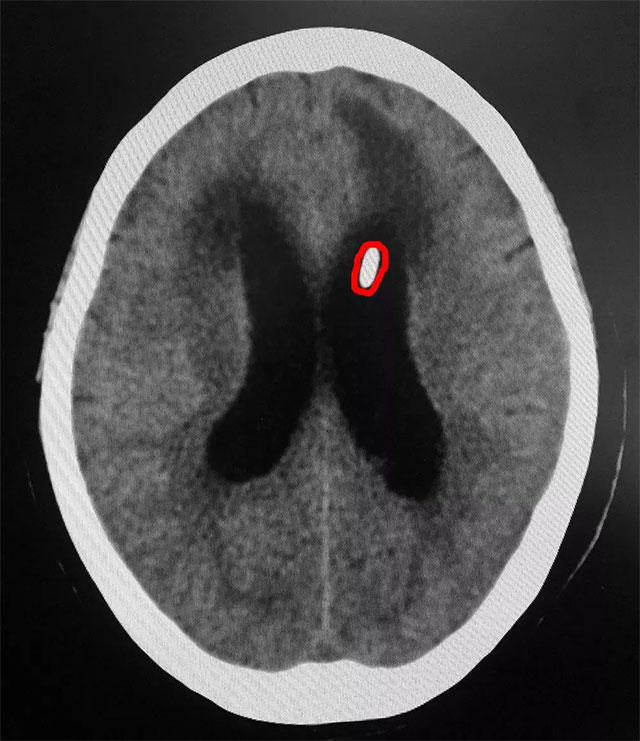

6月22日,上海藍(lán)十字腦科醫(yī)院神經(jīng)外科6B病區(qū)收治了一位重度腦積水患者。一個(gè)月前,患者閆女士(化名)因后交通動(dòng)脈瘤破裂昏迷,在當(dāng)?shù)蒯t(yī)院進(jìn)行了手術(shù),術(shù)后,患者一直處于昏迷狀態(tài),并出現(xiàn)了腦積水等并發(fā)癥。之后完善相關(guān)檢查,患者經(jīng)過(guò)CT確診為交通性腦積水,腦室系統(tǒng)均擴(kuò)張,患者腦積水情況嚴(yán)重,顱內(nèi)壓更是高達(dá)300mmH₂O,達(dá)到腦室腹腔分流手術(shù)的指征。

▲ 患者置入儲(chǔ)液囊后情況較前好轉(zhuǎn)

之后為了更好的治療,潘仁龍主任、吳治群博士專家團(tuán)隊(duì)經(jīng)過(guò)會(huì)診討論,一致認(rèn)為可先對(duì)患者進(jìn)行儲(chǔ)液囊置入術(shù),緩解患者顱內(nèi)高壓。并對(duì)儲(chǔ)液囊置入后患者的情況進(jìn)行評(píng)估,如果患者置入儲(chǔ)液囊后,腦積水情況有所緩解;而關(guān)掉儲(chǔ)液囊后,患者腦室又開始擴(kuò)大,說(shuō)明進(jìn)行腦室腹腔分流術(shù)是非常有必要的。隨后,吳治群博士為患者進(jìn)行了儲(chǔ)液囊置入術(shù),患者腦積水情況較前有所好轉(zhuǎn),但關(guān)掉儲(chǔ)液囊后病情又開始嚴(yán)重。